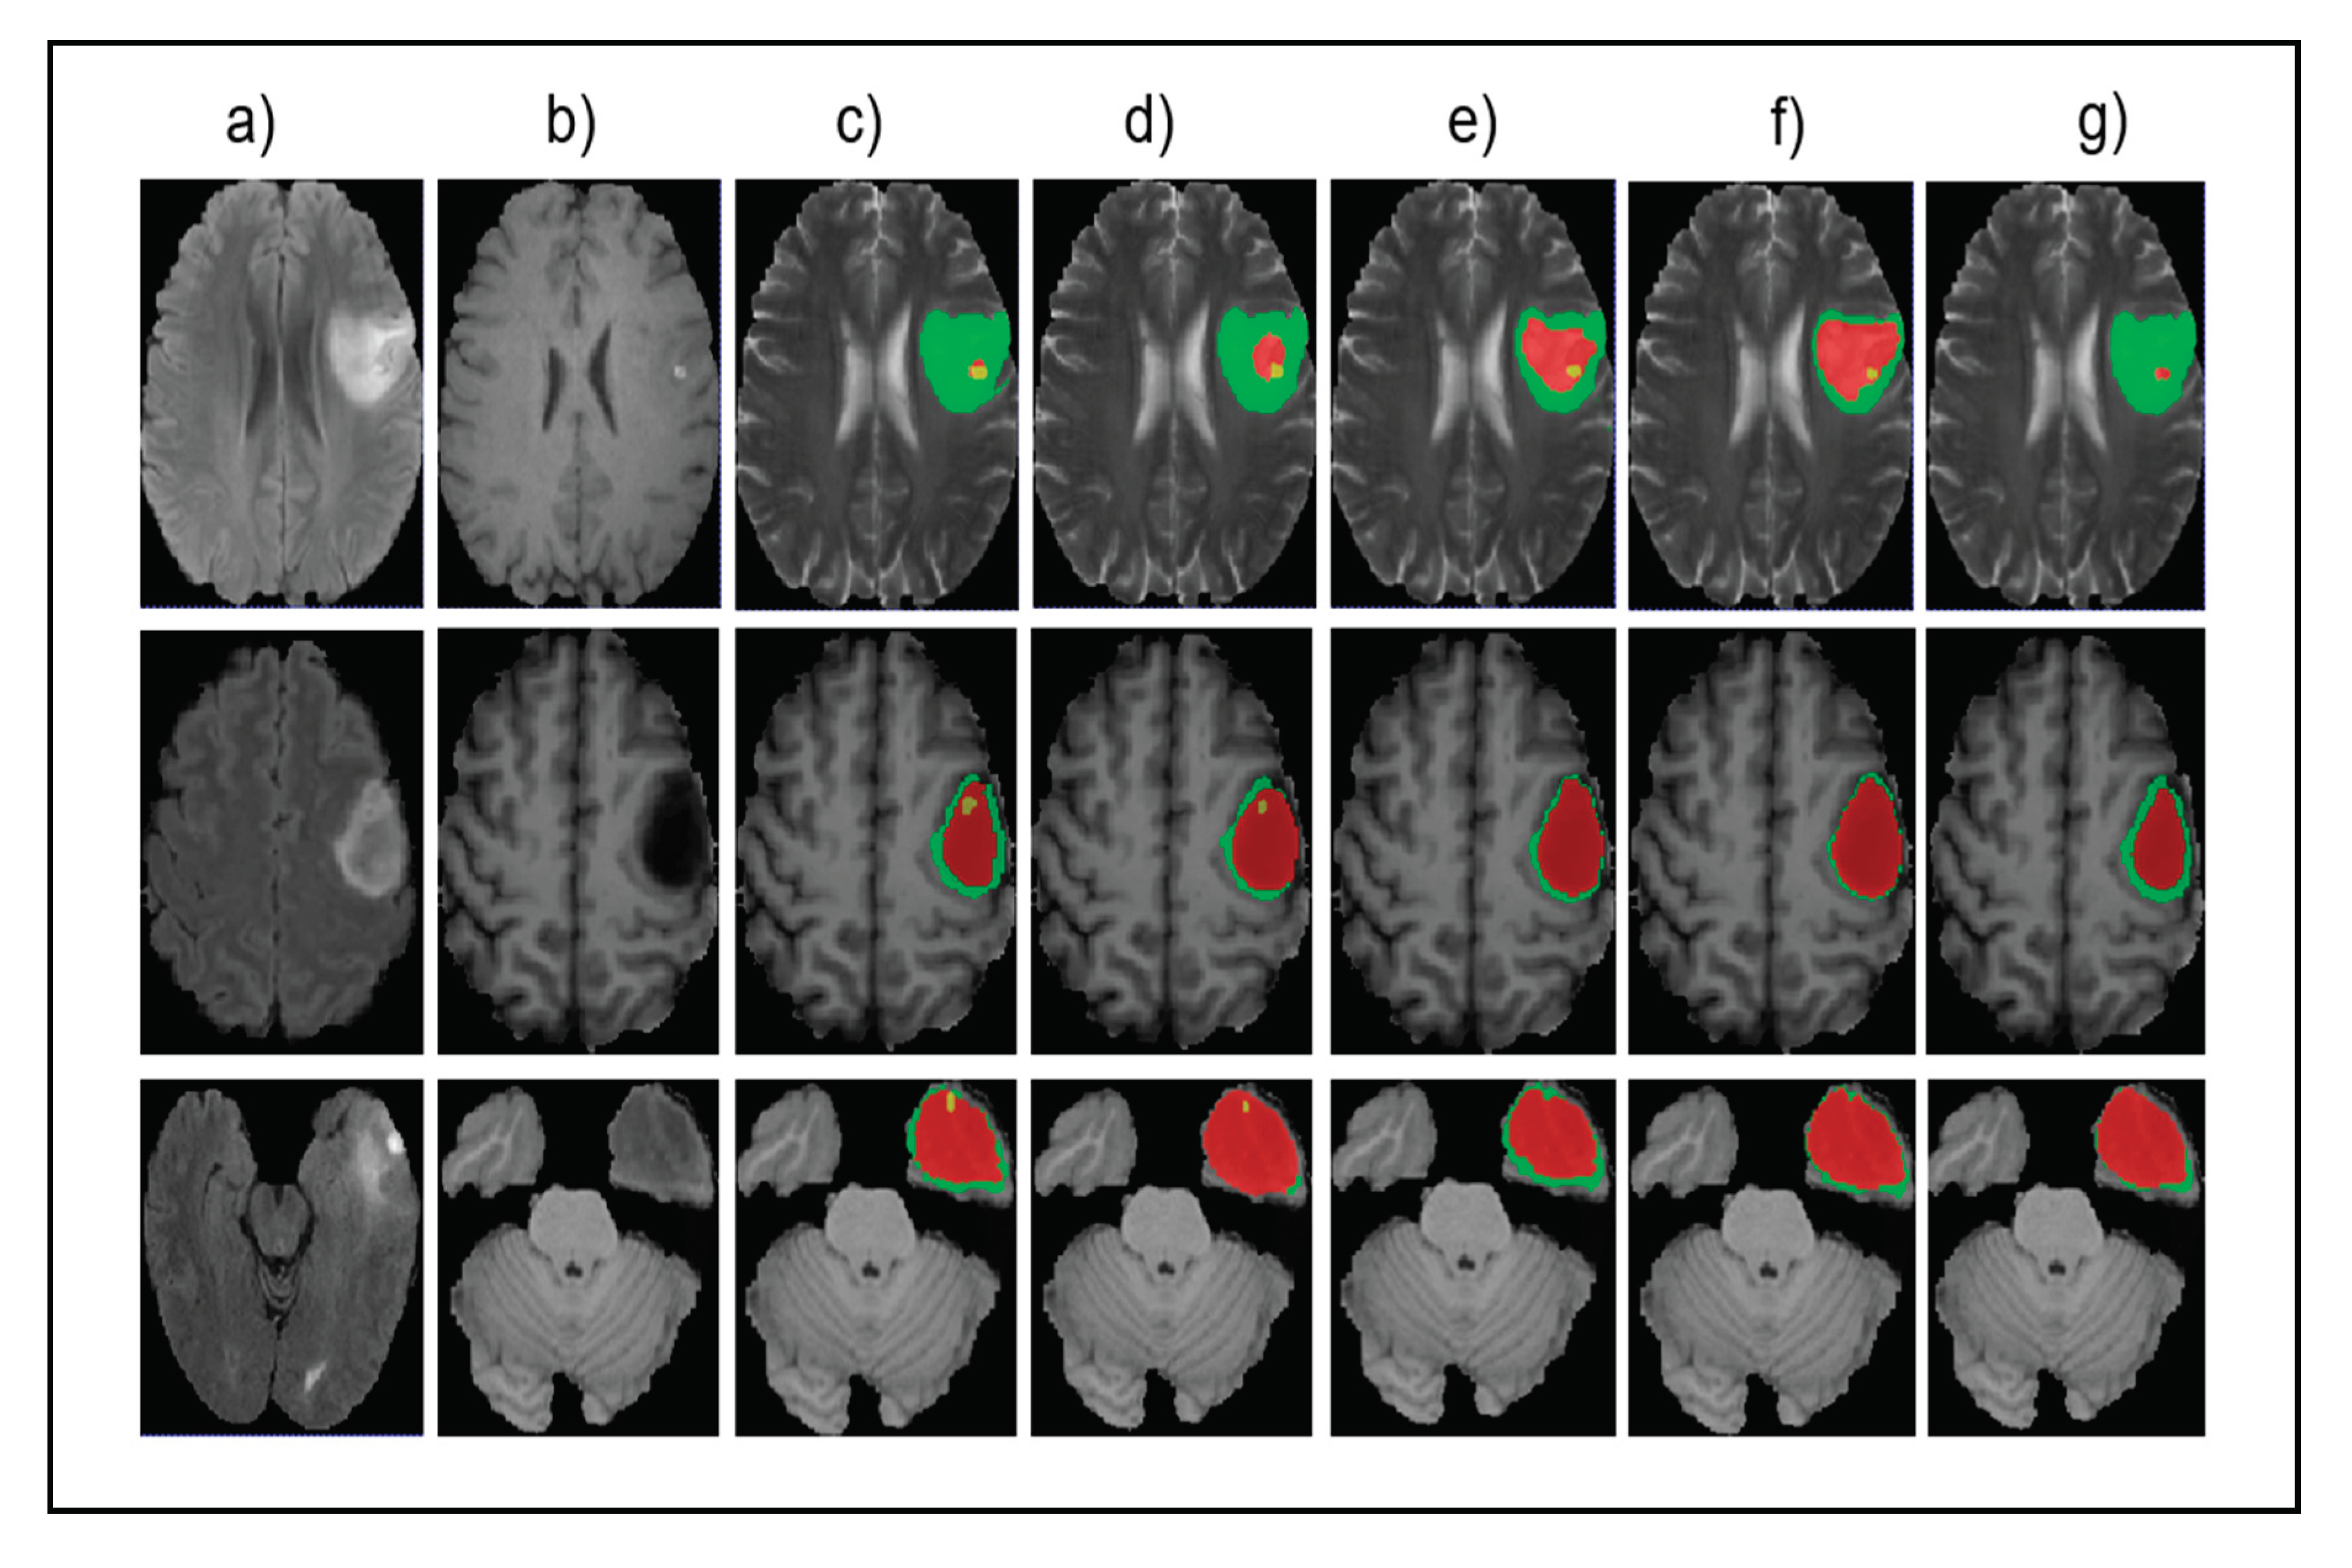

- Most of the previous studies seldom considered the small-sized tumors, which have a significant impact on finding early-stage cancers. This paper focuses on solving the problem of accurately identifying multiscale tumors, especially very small-sized tumors in the brain.

- Instead of using heavyweight networks with multiresolution or multiple kernel sizes, we propose a novel approach for better segmentation of small tumors by dilated convolution and multi-task learning. Using multi-task learning for hierarchical analysis is relatively new and has never been tried before small-tumor detection or segmentation.

4.5. Results and Analysis

4.5.1. Small Tumor Segmentation Performance

4.5.2. Overall Segmentation Performance